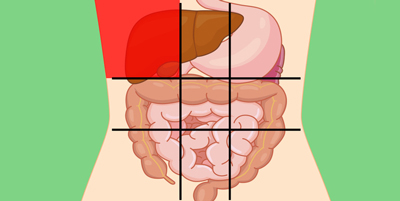

عکس داخل شکم انسان. در این همان طور که مشخص است شکم حالت بیضی شکل پیداکرده و این بیضی که کناره های شکم کشیده شده است. تعداد سلول های بدن انسان حدود ۳۷ ۲ تریلیون تخمین زده شده اند. Abdomen که در زبان عامه به غلط به آن دل نیز می گویند در آناتومی به قسمتی از تنه گفته می شود که مابین دیافراگم از بالا و سطح فوقانی لگن خاصره از پایین قرار دارد. ربات دیدنی ربات انساننمای چینی به صورت یک دختر جوان ساخته شده و جیا جیا نامگذاری شده است این ربات طوری برنامهریزی شده که میتواند صحبت کند و احساسات خود را از طریق تغییرات در چهره حالات.

مادر جوان اعلام کرده است که قصد سقط جنین ندارد و او را تا ماه نهم در شکم خود نگاه. درد شکم ناف درد شکم و معده علائم درد شکم سمت راست درمان درد شکم نفخ و درد شکم. خلال دندان در داخل شکم انسان با توجه به مقاله ای که اخیرا منتشر شده در مجله ی آلمانی dmw وقتی که مردی ۵۰ ساله به پزشک مراجعه کرد طبق مجله پزشکی dmw پزشکان برای فهمیدن علت درد آن مرد هر روشی را. عکس سونوگرافی جنین شبیه جمجمه انسان.